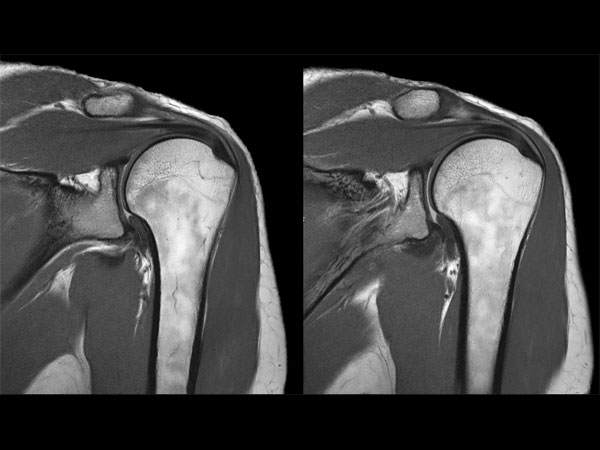

Shoulder imaging with dS Flex coil

Used Solution

• System

• Coil